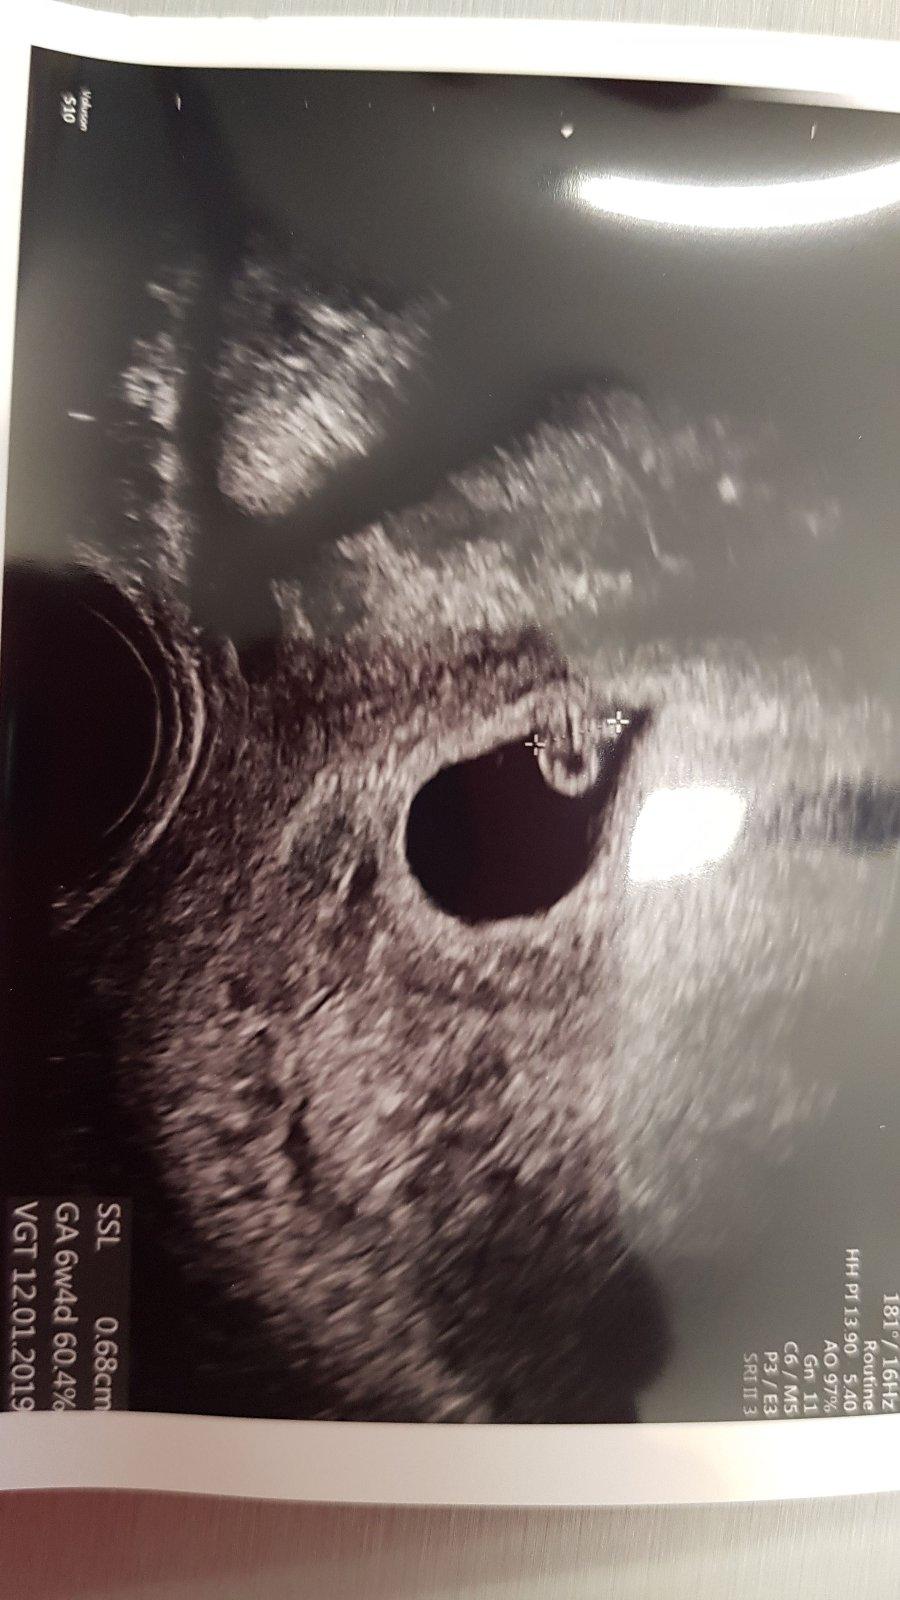

No já jsem 15.3 musela podstoupit revizi pro ZT v 10tt (miminko odpovídalo jen 6+2tt) takže proto se teď nikam neženu brzy 🙂